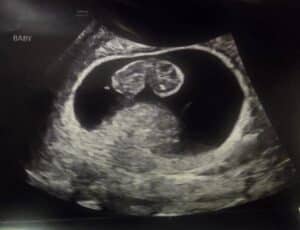

Essure Reversal Surgery Worked, We Are Having A Boy!

Essure Reversal Worked!

We are having a BOY!!!!

Patient age: 35

Tubal ligation type: Essure

Patient hometown: Pound, Virginia